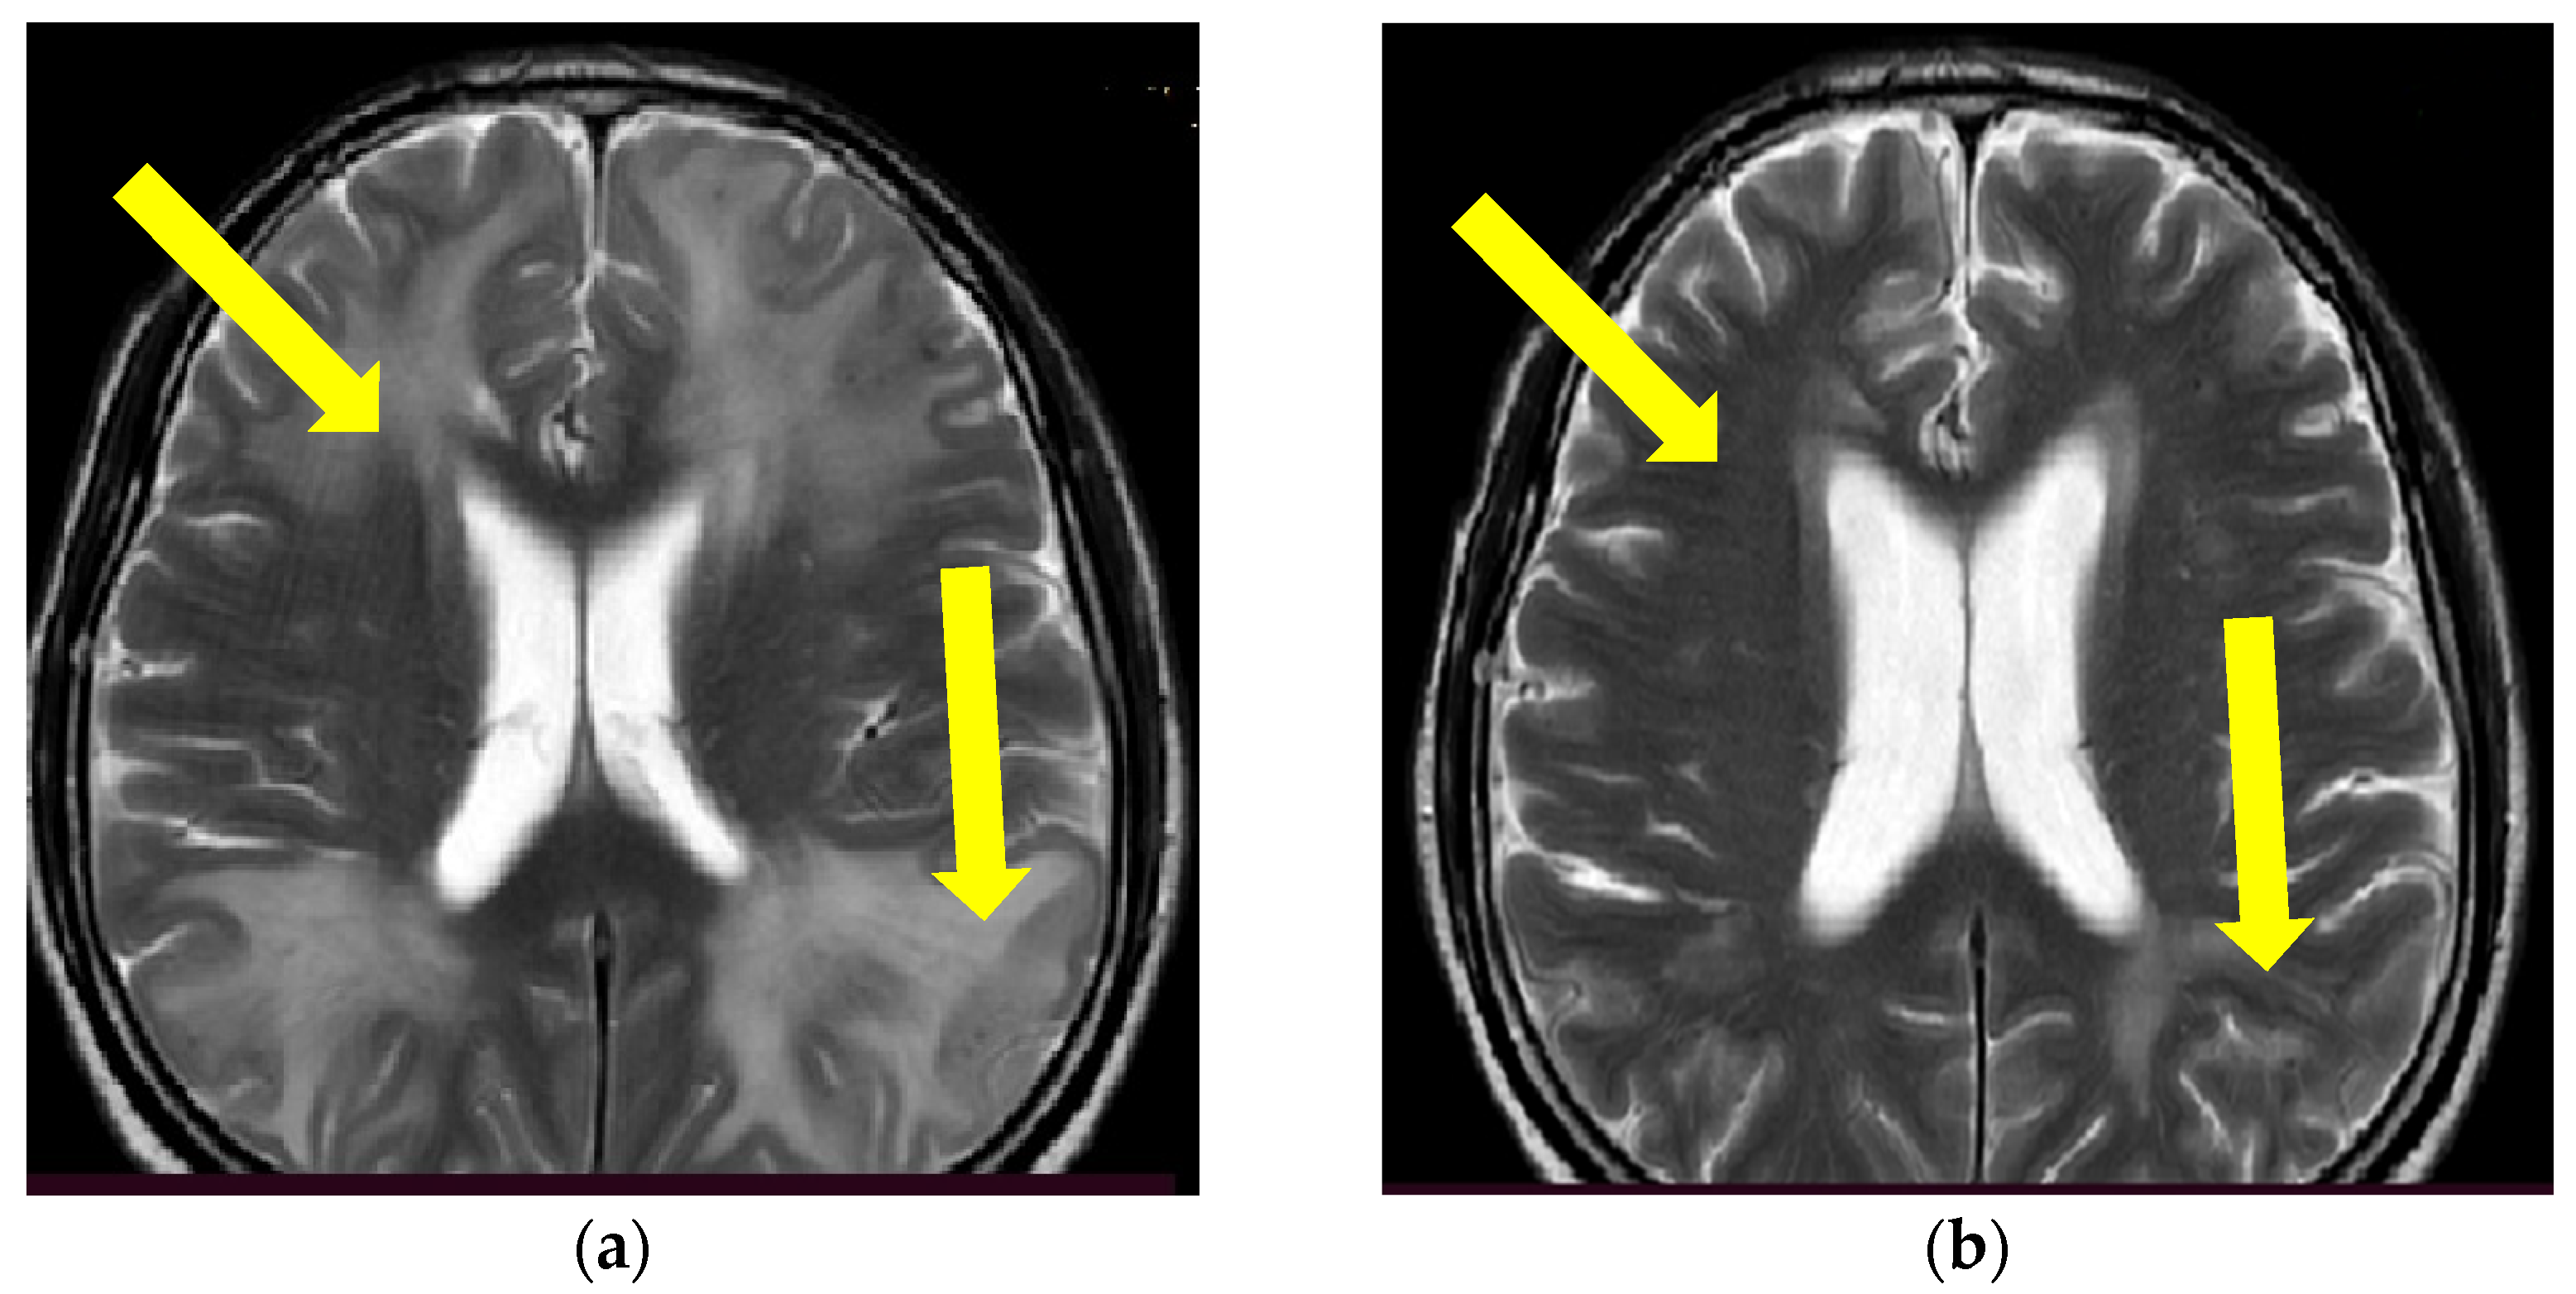

Figure 1.

Initial brain MR T2 sequence at admission and before therapy initiation (a) and one month after therapy initiation (b). Yellow arrows are showing confluent and extensive bilateral periventricular hyperintensities in (a) and reduction of hyperintensities of the same locations on (b). (Patient No. 1).

Since the patient fulfilled all the criteria for the diagnosis of probable CAA-ri (age > 40 years, decreased consciousness, with the presence of behavioral changes and focal neurologic deficit, MR signs of asymmetric WMH lesions and cerebral microbleeds, with the absence of other possible causes), the patient was initially treated with antihypertensive and anti-edematous therapy, together with IV dexamethasone (8 mg/daily) for 10 days, followed by pulse methylprednisolone therapy (1000 mg/day) for 5 days, after which oral prednisone (1 mg/kg) was slowly tapered down. The patient’s neurological status improved and he showed very discrete hemiparesis and normal gait, and the patient was alert and oriented. A neurological examination was almost without significant impairment and sequelae. A control CSF examination was performed, where normal levels of protein and glycose were detected. A normal cell count was present, and no OCB were registered. Control brain MR showed edema reduction with less extended WMH lesions (Figure 1 and Figure 2). The post treatment neuropsychological examination was without significant impairment.